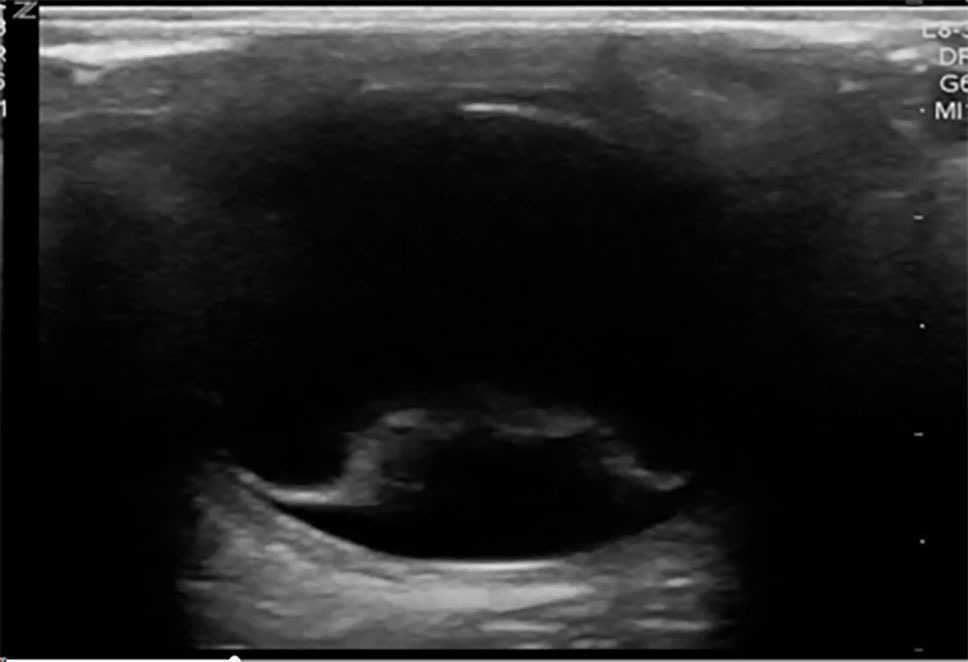

Additional methods of evaluating the posterior segment of the eye may include digital fundus photography and ultrasound. Digital fundus photography has been shown to have reasonable sensitivity and high specificity and can be interpreted remotely or asynchronously by an ophthalmologist, when linked into the electronic health record.33 A detailed fundoscopic exam can detect evidence of vascular disease, such as a Hollenhorst plaque, which can lead the clinician toward a diagnosis of amaurosis fugax secondary to ischemia. As mentioned earlier, POCUS has demonstrated high sensitivity and specificity for diagnosing retinal detachments and also can be used to evaluate for other ocular pathologies.30,34 Using POCUS, retinal detachments will appear as wavy lines tethered to the posterior segment of the eye. (See Figure 2.) Vitreous hemorrhages will display a sign called the “washing machine sign,” in which the echogenic blood will swirl when the globe is moved from side to side and typically is not tethered to the posterior segment. (See Figure 3.) To see an example of this, visit: https://emottawablog.com/2022/08/ocular-pocus-keep-your-prize-on-the-eyes/#:~:text=Vitreous%20hemorrhage%20occurs%20when%20extravasated,a%20“washing%20machine%20sign”.

Figure 2. Ocular POCUS Showing Retinal Detachment |

![]() |

Point-of-care ultrasound (POCUS) showing retinal detachment with wavy hyperdense line tethered to the posterior segment of the eye Courtesy of Jodi Jones, MD |